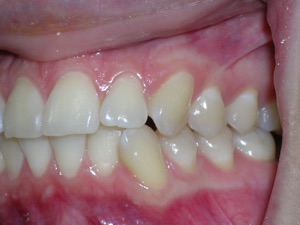

Here are the results. We used a bonded retainer on the bottom teeth.